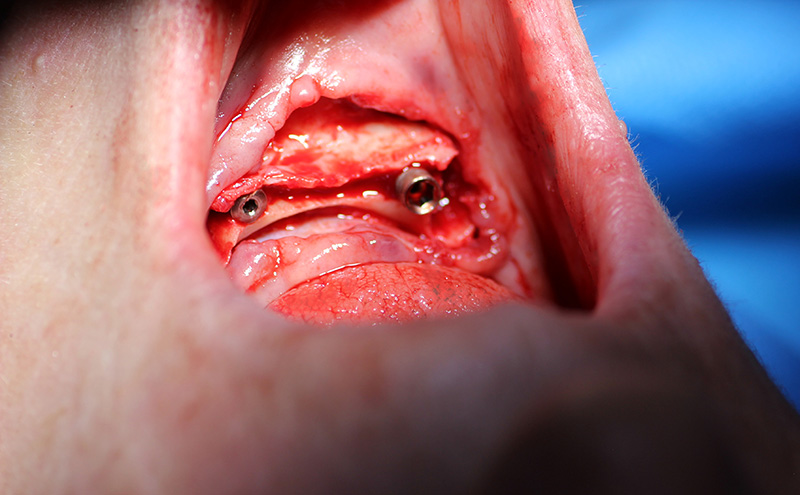

Мастер-Класс «Одномоментная Имплантация С Аугментацией Кости», с использованием имплантатов Alfa Gate

25-ого октября в учебном центре Стом-Лайн был проведен мастер-класс на тему «Одномоментная имплантация с аугментацией (наращиванием) кости, с использованием имплантатов Alfa Gate Dental Implants». Мастер-класс провел главный врач-стоматолог клиники «Нюанс» в Москве Мхитар Казарян.

Мастер-класс начался с обсуждения предстоящей операции и исследования компьютерной томографии, после чего участники смогли присутствовать на операции или следить за ней из учебного центра.